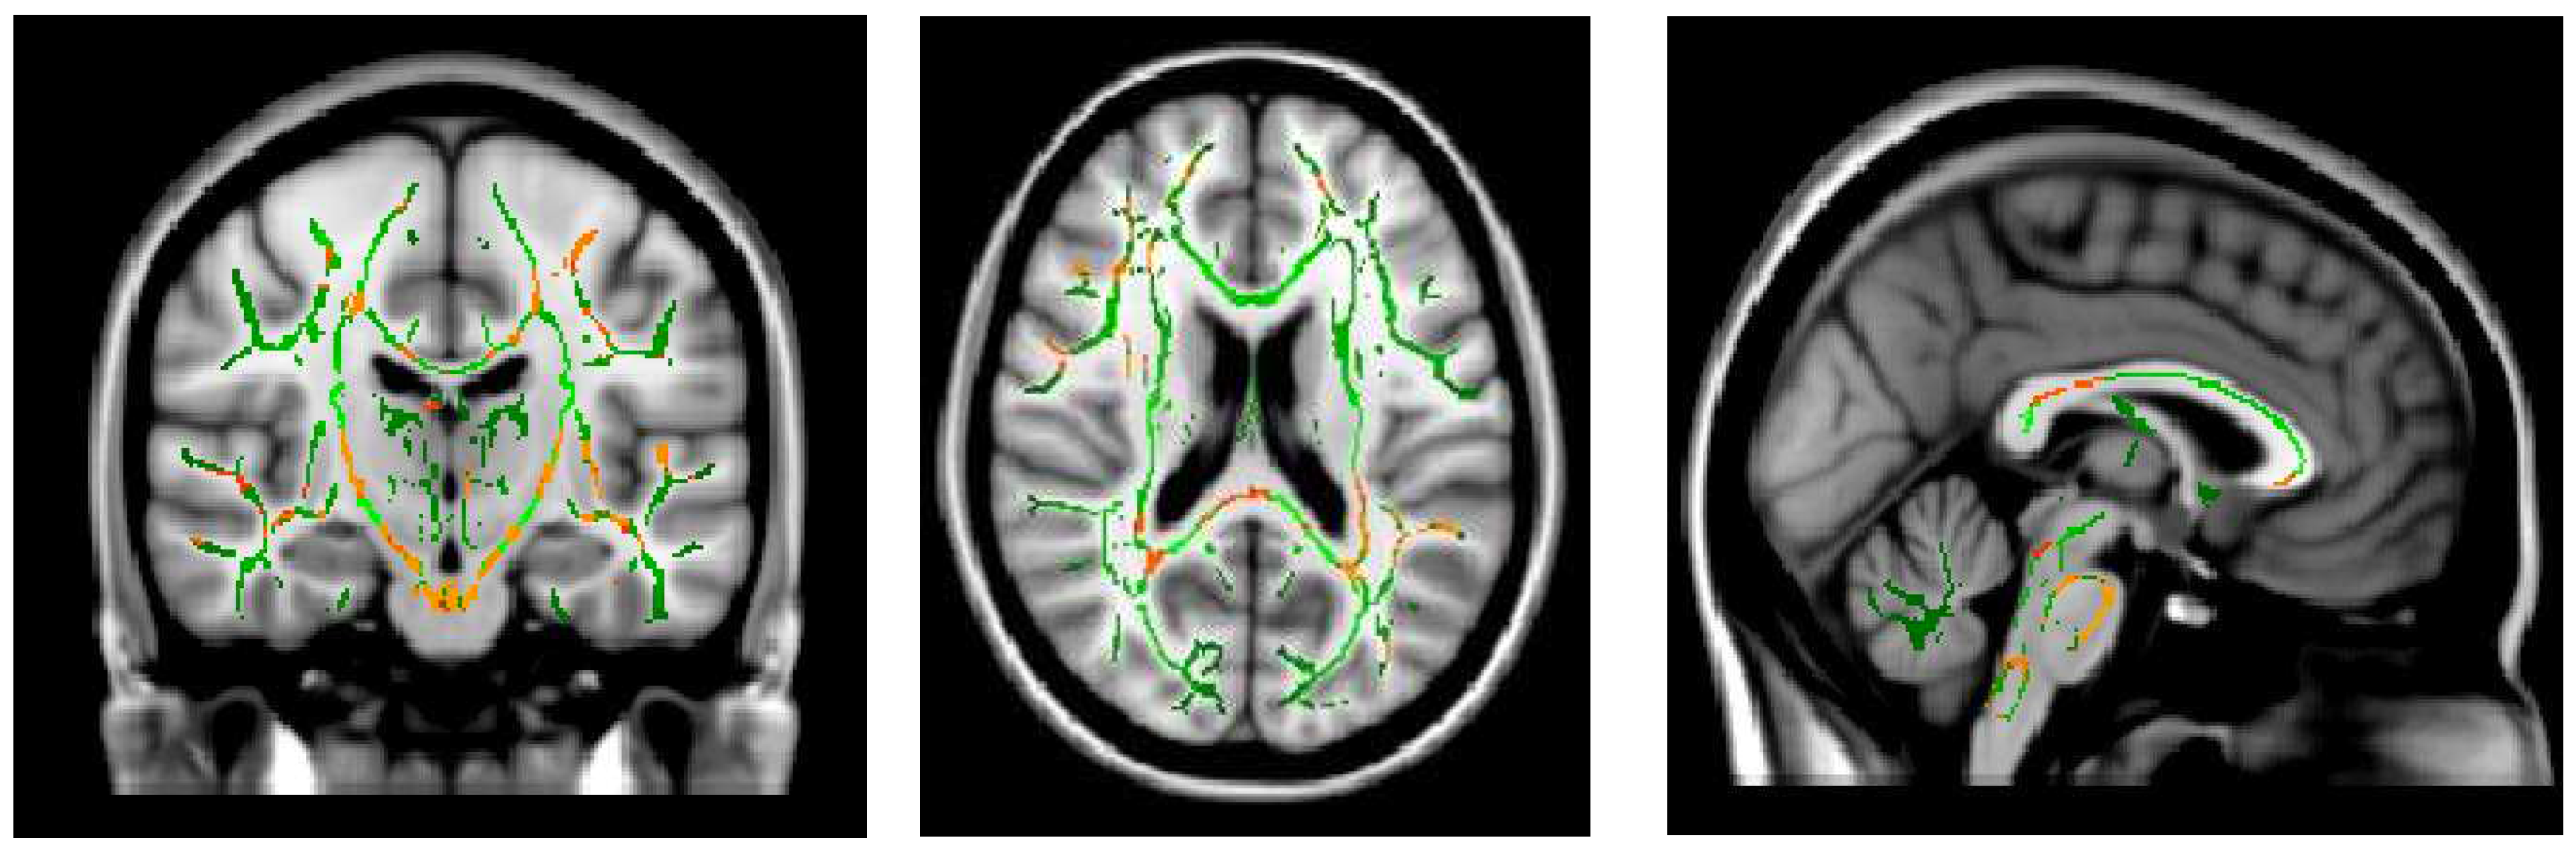

- Shibata Y, Ishiyama S, Matsushita A: White matter diffusion abnormalities in migraine and medication overuse headache: A 1.5-Tesla tract-based spatial statistics study. Clinical Neurology and Neurosurgery 2018, 174, 167–173. [CrossRef]

- Smith SM: Tract-based spatial statistics. NeuroImage 2006, 31, 1487–1505.